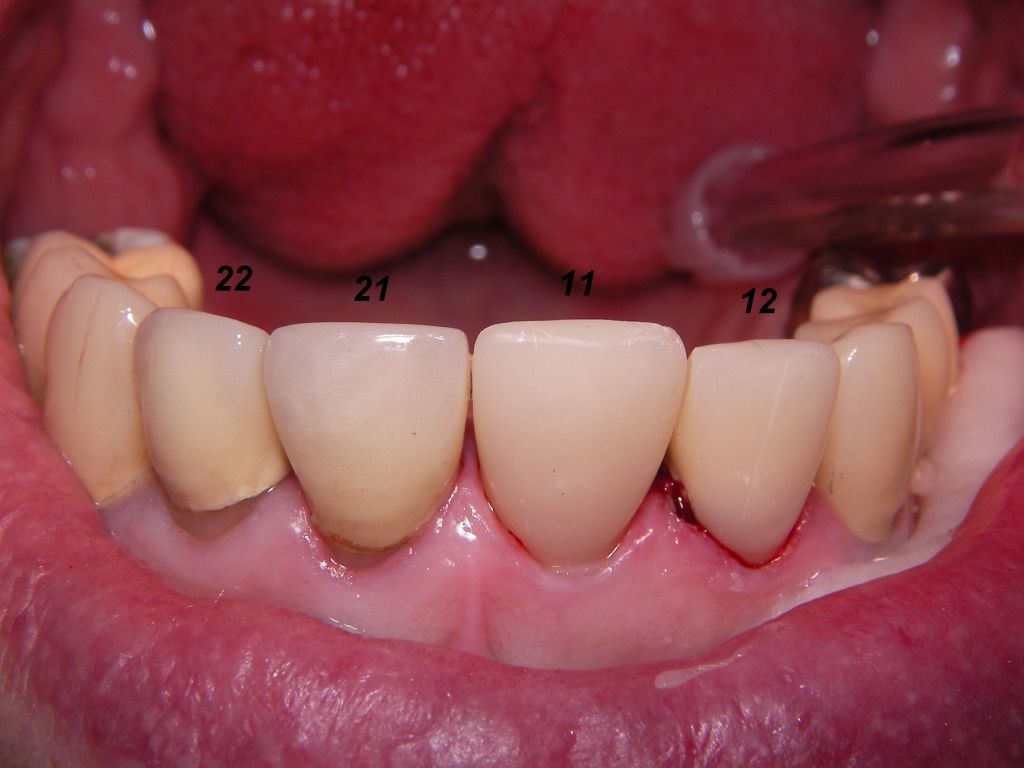

Allerdings kann man diesen Metallrand auch sehr schmal gestalten, wie das folgende Beispiel zeigt. Wegen der starken Zerstörungen mußte der Kronenrand tief unter das Zahnfleisch gelegt werden. Das ist einerseits ungünstig, weil es Zahnfleischentzündungen fördern kann (die hier aber nicht zu sehen sind), andererseits günstig, weil nicht zu befürchten ist, daß das Zahnfleisch so weit zurückgehen wird, daß man den Kronenrand sehen wird.

Weil auch die anderen Schneidezahnkronen (12-22) durch Randreparaturen und den schlechten Randschluß erneuerungsbedürftig aussahen, wurden 4 Einzelkronen geplant. Vorher hieß es aber noch, die schlechte Wurzelfüllung im Zahn 12 (Röntgenbild links) besser zu machen. Hierfür wurden am 17.2.06 die alten Kronen 11 und 12 entfernt. Rechts das Bild nach Entfernung von alten Füllungen und Karies.